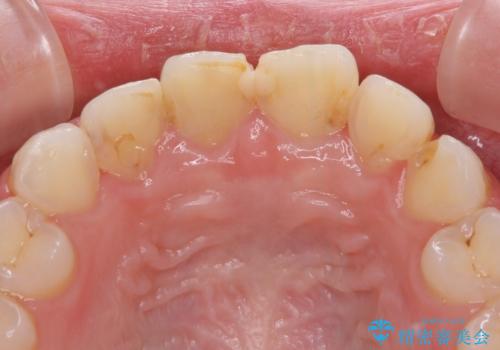

- 前歯の歯並びと虫歯を気にして来院された患者様です。

上下前歯の歯列不正はインビザラインにより歯列を整え、その後に、前歯5本をオールセラミッククラウンにて補綴治療することとしました。

矯正治療前に前歯のむし歯治療を行ったものの、樹脂で充填するには虫歯が広範囲であったため、審美的に問題がありました。